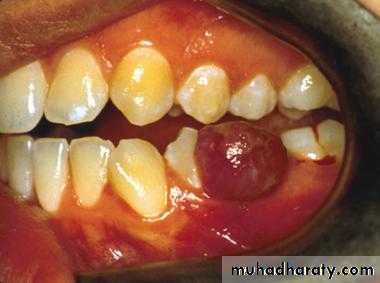

pyogenic granuloma

• Is a benign, elevated, and capillary-rich lesionIs, soft, red or purple mass on the lips, interdental papilla, or buccal mucosa .• It may occur in the skin.

• The cause is thought to be local irritation, hormonal factor or trauma.

• When located at the gingiva of pregnant women, the term pregnancy tumor may be used.

• An oral pyogenic granuloma most frequently involves the gingiva.

• The lower lip and the dorsal surface of the tongue are rather common sites as well.• The lesion is usually pedunculated or sessile, and the surface is often ulcerated.

• The size of the lesion's diameter may vary from 0.5 to 2 cm or more.

• Sometimes rising the question of whether one is dealing primarily with a vascular lesion with secondary signs of inflammation or with an inflammatory condition.

• Mitotic activity may be abundant and should not be mistaken as a sign of malignancy.

• Surgery is the management of choice. Recurrence rare.